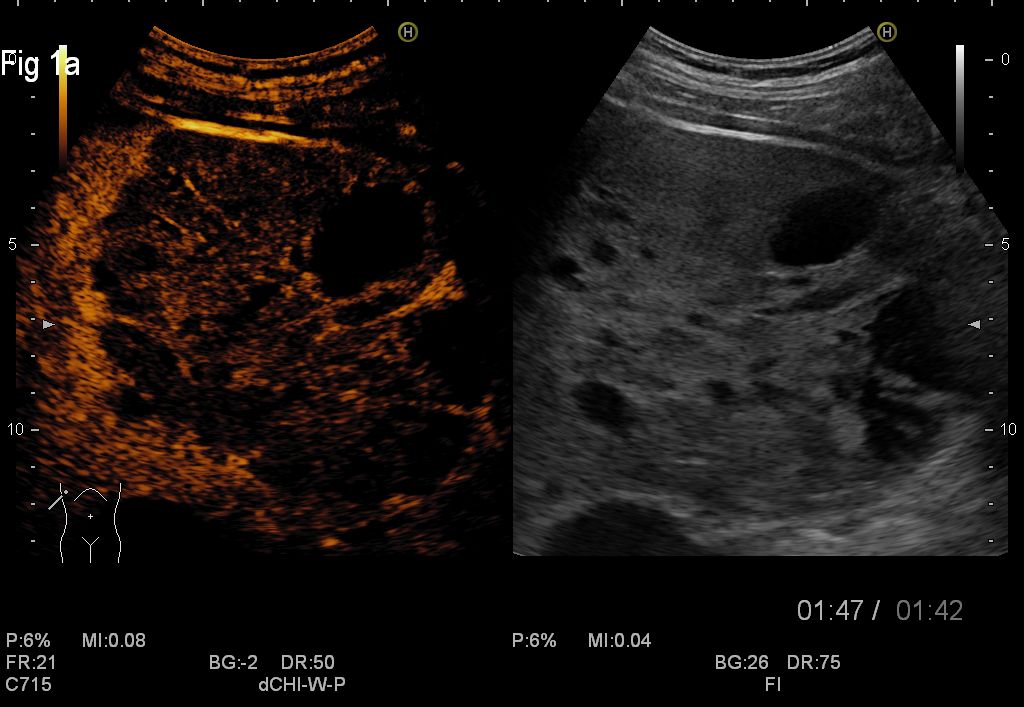

Figure 1a,1b. CEUS of the secondary cystic liver masses in the late venous phase

For this case, CEUS supported the diagnosis of cystic metastases, whilst studies showed previously that CEUS represents a useful method in clinical practice and clearly improves the differential diagnosis between malignant and benign liver lesions detected on standard ultrasonography, with a positive predictive value of 95.4% and negative predictive value of 95.9%. The main criteria for malignancy on CEUS is contrast wash-out in the late portal venous phase whereas benign lessons typically remain iso-enhancing with the surrounding normal liver tissue (5,6). Metastases usually show a brief arterial hypervascularity and complete rapid wash-out, which can improve detection during the portal phase (7). Neoplastic cysts such as cystic metastasis can be characterized on CEUS by sensitive real-time demonstration of vascular flow within the septa or solid component. Non-neoplastic complex cysts such as hemorrhagic cysts or hydatid cysts show the absence of intralesional enhancement on CEUS, thus confirming their non-neoplastic nature (8).